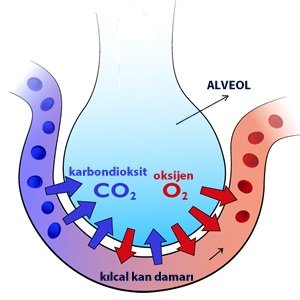

Akciğerlerin yapısında, çok ince duvarları olan alveoller bulunur.

Alveollerin çevresi çok sayıdaki kılcal damarlarla çevrilidir.

Akciğerle kan arasındaki gaz alışverişi alveollerde gerçekleşir.

Alveoller

Küçük kan dolaşımında, vücutta oksijence fakirleşen kan temizlenmek üzere akciğerlerdeki alveollere taşınır. Alveollerin etrafı kılcal damarlarla çevrilidir. Kılcal damarlardaki oksijence fakir kan alveollerdeki oksijeni alır, karbondioksiti alveollere verir. Oksijence zengin kan akciğer toplardamarı ile kalbe dönerek tüm vücuda dağıtılır.